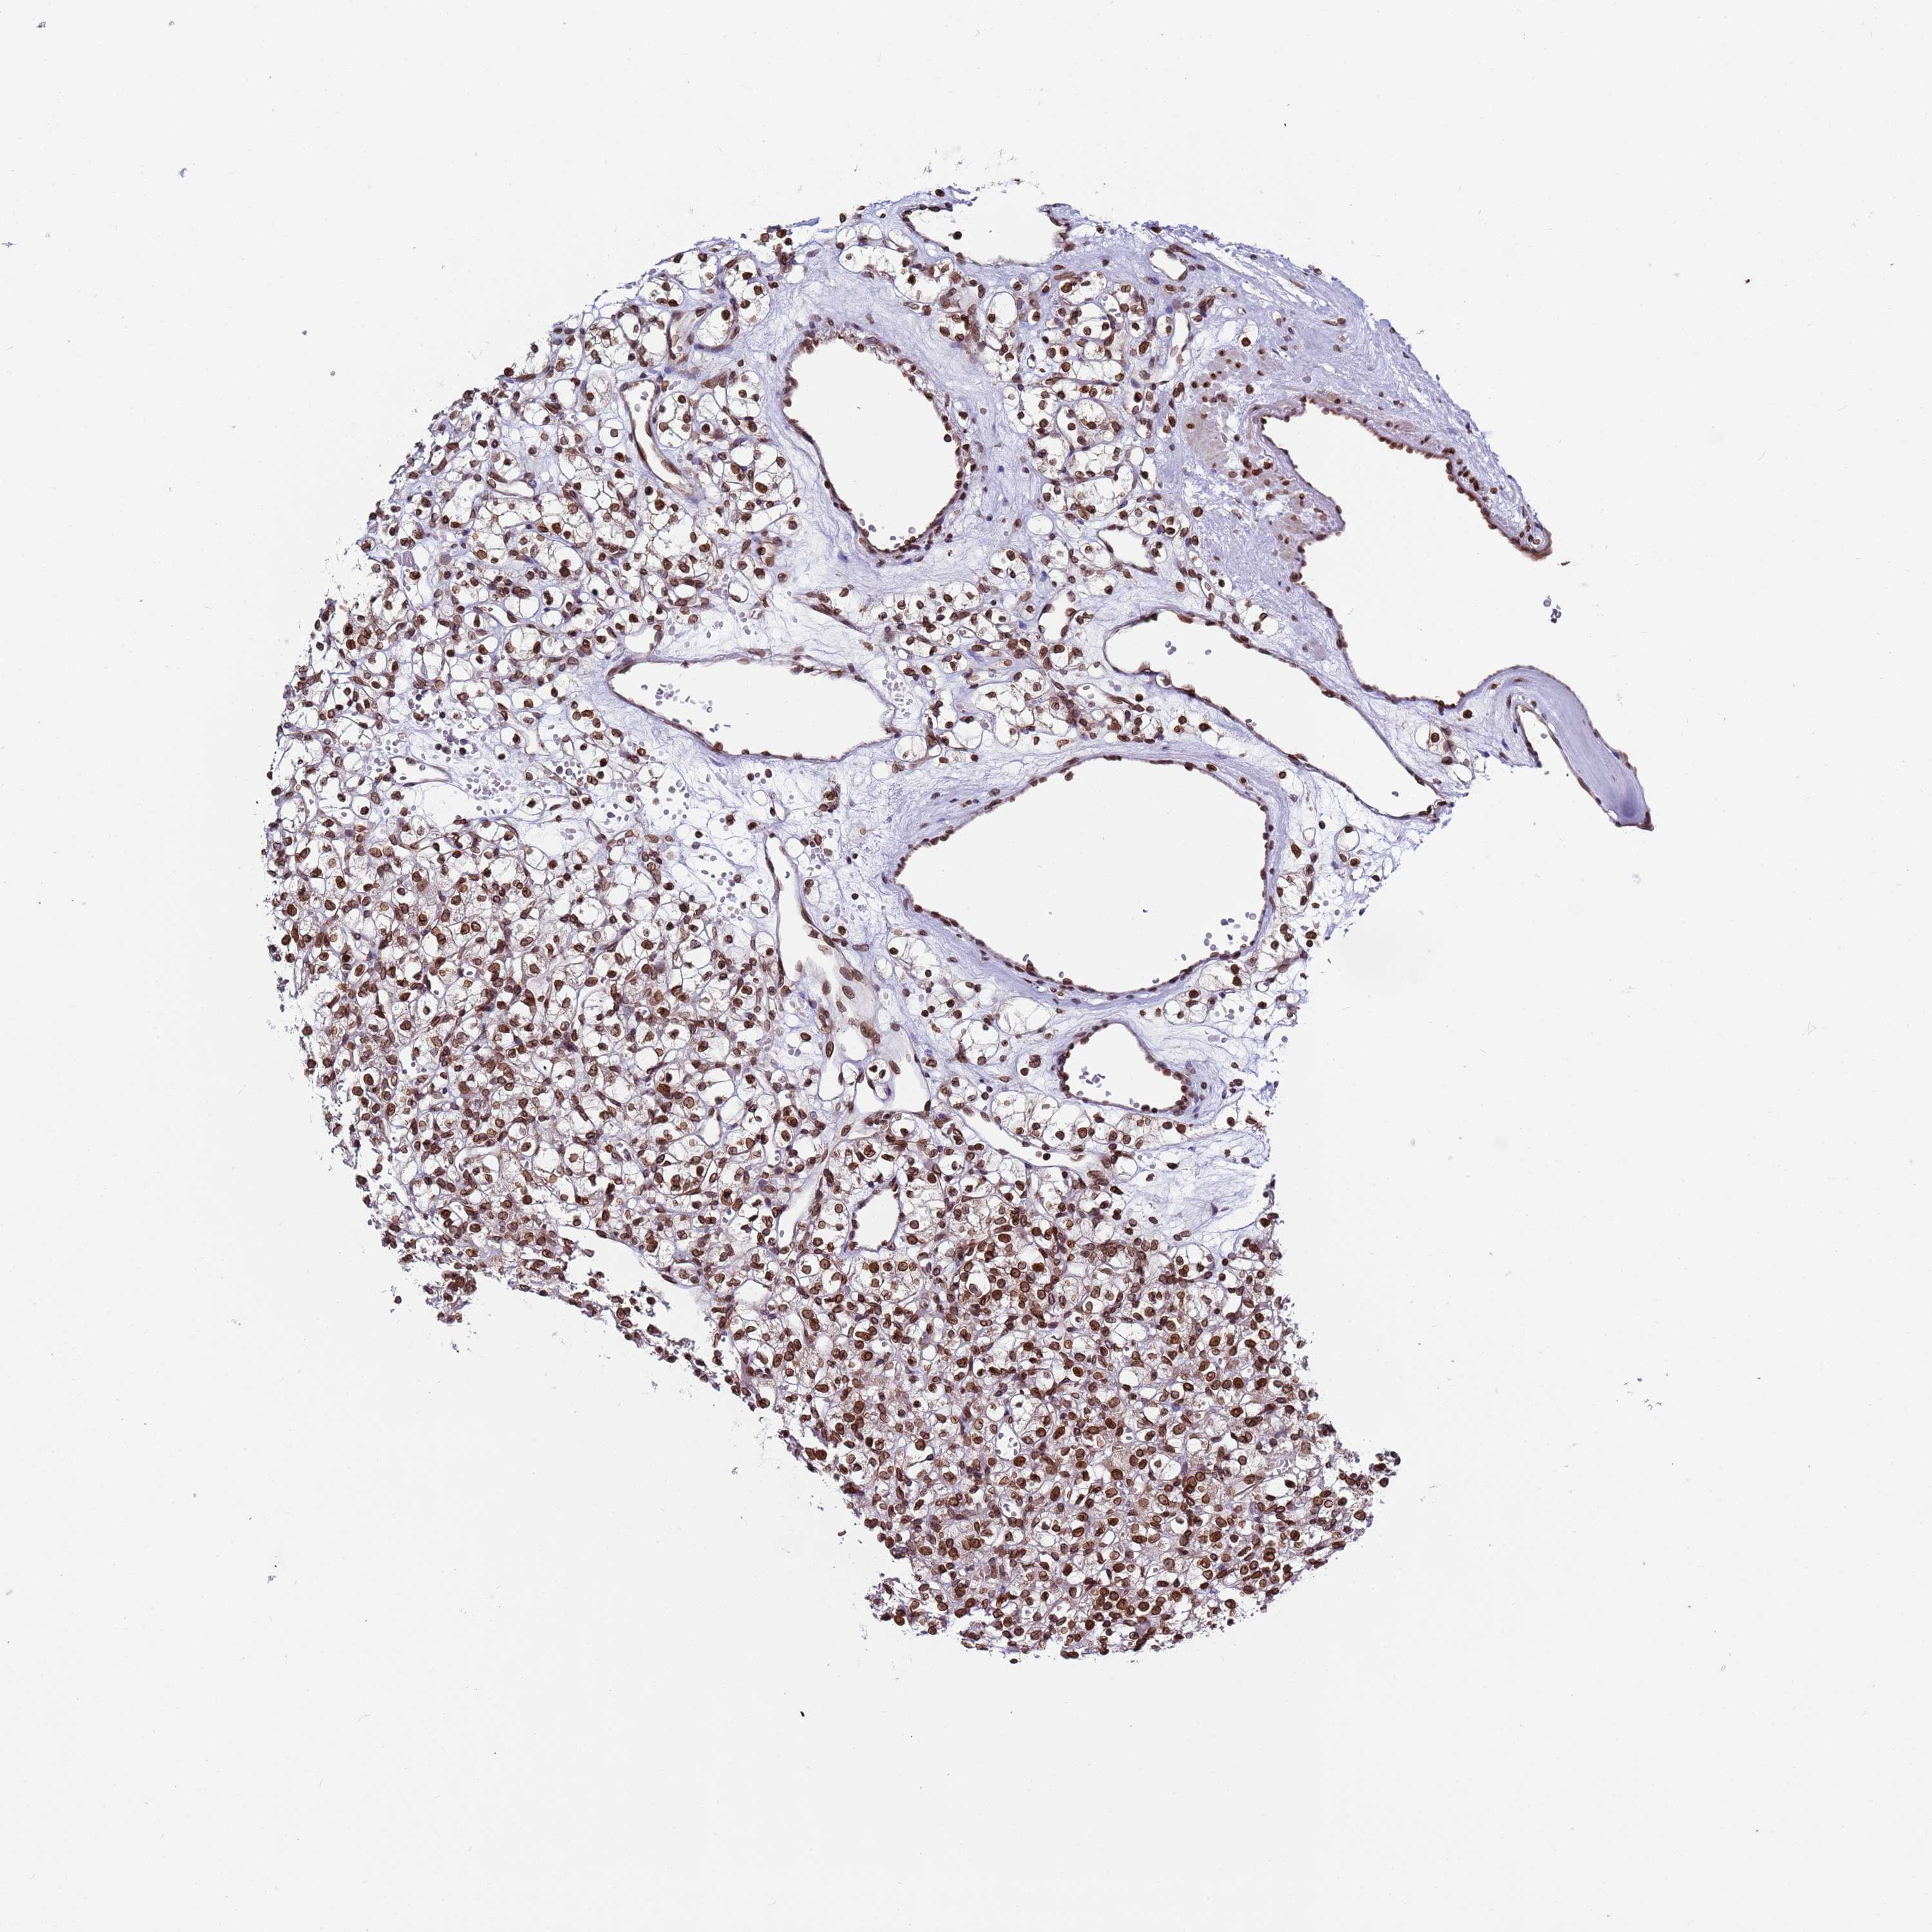

KIDNEY RENAL CLEAR CELL CARCINOMA (VALIDATION) - Interactive survival scatter ploti

The Survival Scatter plot shows the clinical status (i.e. dead or alive) for all individuals in the patient cohort, based on the same data that underlies the corresponding Kaplan-Meier plots. Patients that are alive at last time for follow-up are shown in blue and patients who have died during the study are shown in red.

The x-axis shows the expression levels (FPKM) of the investigated gene in the tumor tissue at the time of diagnosis. The y-axis shows the follow-up time after diagnosis (years). Both axes are complimented with kernel density curves demonstrating the data density over the axes. The top density plot shows the expression levels (FPKM) distribution among dead (red) and alive patients (blue). The right density plot shows the data density of the survived years of dead patients with high and low expression levels respectively, stratified using the cutoff indicated by the vertical dashed line through the Survival Scatter plot. This cutoff is automatically defined based on the FPKM cutoff that minimizes the p-score. The cutoff can be changed by dragging the vertical line or by entering a cutoff value in the square labeled "Current cut-off".

Under the Survival Scatter plot the p-score landscape (black curve; left axis) is shown together with dead median separation (red curve; right axis). Dead median separation is the difference in median mRNA expression between patients who have died with high and low expression, respectively. It is calculated as follows: median FPKM expression of dead patients with high expression - median FPKM expression of dead patients with low expression. This is intended to aid the user in visually exploring custom cutoffs and the associated p-scores and dead median separation.

Individual patient data is displayed and can be filtered by clicking on one or more of the category buttons on the top of the page. Categories describing expression level and patient information include: high, low, alive, dead, female, male and tumor stages. The scale of the x-axis can be toggled between linear and log-scale by clicking on the "x log" button. Mouse-over function shows TCGA ID, patient information and mRNA expression (FPKM) for each patient.

& Survival analysisi

Kaplan-Meier plots summarize results from analysis of correlation between mRNA expression level and patient survival. Patients were divided based on level of expression into one of the two groups "low" (under cut off) or "high" (over cut off). X-axis shows time for survival (years) and y-axis shows the probability of survival, where 1.0 corresponds to 100 percent.

TOR1AIP1 is not prognostic in Kidney Renal Clear Cell Carcinoma (validation)

Best expression cut offi

Based on the FPKM value of each gene, patients were classified into two groups and association between prognosis (survival) and gene expression (FPKM) was examined. The best expression cut-off refers the FPKM value that yields maximal difference with regard to survival between the two groups at the lowest log-rank P-value. Best expression cut-off was selected based on survival analysis .

When clicking on this number, the vertical dashed line indicating cut-off, the interactive survival plot, and the Kaplan-Meier curve will be adjusted to show results based on the best expression cut-off.

: 41.45

P scorei

Log-rank P value for Kaplan-Meier plot showing results from analysis of correlation between mRNA expression level and patient survival.

N/A

TCGA RNA samplesi

RNA-seq data is reported as average FPKM (number Fragments Per Kilobase of exon per Million reads), generated by the The Cancer Genome Atlas (TCGA) .

Normal distribution across the dataset is visualized with box plots, shown as median and 25th and 75th percentiles. Points are displayed as outliers if they are above or below 1.5 times the interquartile range. FPKM values of the individual samples are presented next to the box plot.

Average pTPM 48.4

Number of samples 100